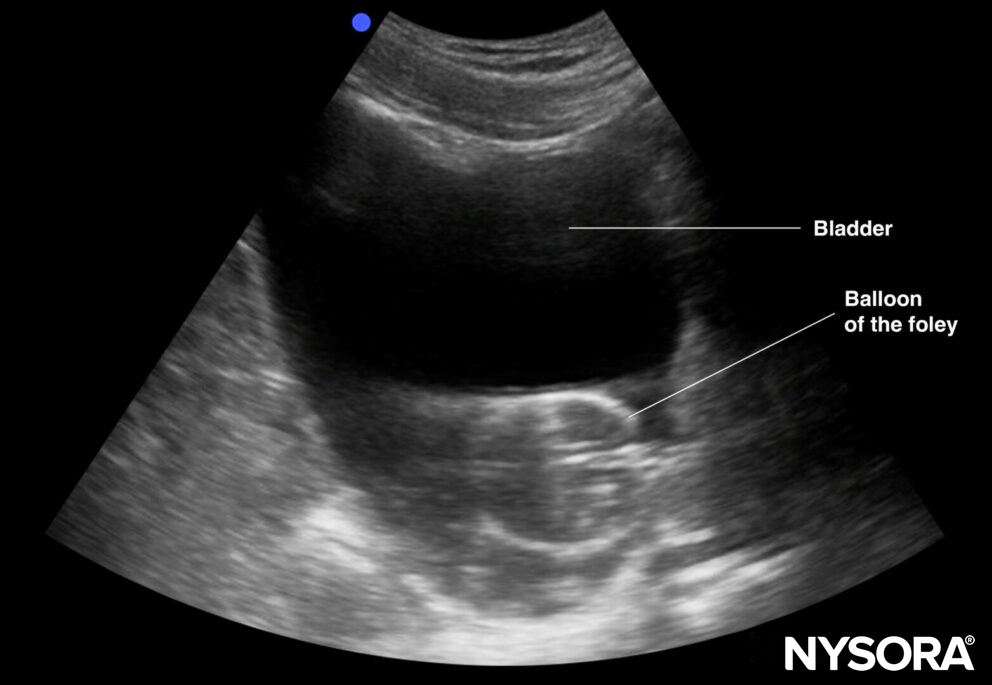

Foley catheter position assessment

A correctly positioned urinary catheter will result in an empty bladder or a non-distended bladder with an intraluminal balloon. If the balloon is surrounded by hypoechogenic fluid, the Foley may be obstructed.

Endoluminal balloon in an obstructed Foley catheter.

Ultrasound of the bladder can guide troubleshooting for difficult catheterization or when there is no urinary flow.